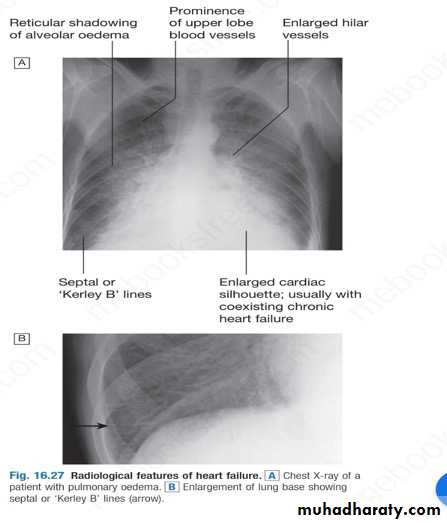

CXRA chest X-ray should be performed in all cases. This may show abnormal distension of the upper lobe pulmonary veins with the patient in the erect position. Vascularity of the lung fields becomes more prominent and the right and left pulmonary arteries dilate.

Subsequently, interstitial oedema causes thickened interlobular septa and dilated lymphatics. These are evident as septal or kerely B line.

More advanced changes due to alveolar oedema cause a hazy opacification spreading from the hilar regions, and pleural effusions